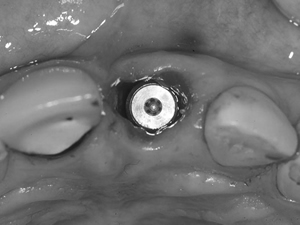

インプラントが骨と結合した後に、アバットメントを装着しました。左のクラウンも除去しています。

4.

左右の前歯にオールセラミックスクラウンを装着しました。写真は、2004年にインプラントを行ってから5年半経った状態です。定期的にメインテナンスを行い、インプラントもクラウンも良好な状態です。